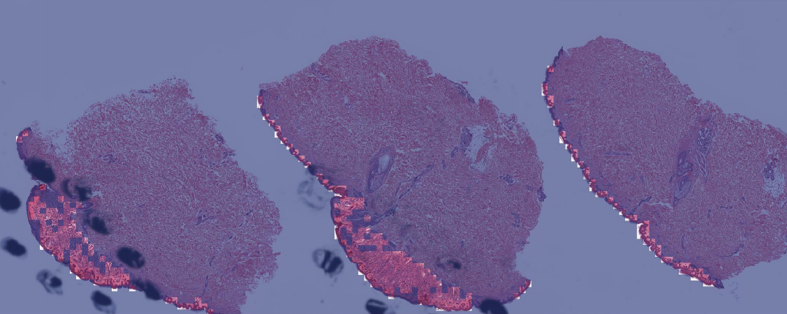

Explanations for the figures. Figure 2 shows one representative sample of annotations (black dot regions) as well as without annotations. Visualization maps of two samples from the melanocytic skin tumor dataset are shown in figure 3 and figure 4. Figure 3 shows the three types of figures of the largest ROI region from melanoma found by the proposed method. Figure 4 is the same for the nevus sample. The overlap map highlights top-ranked patches in a WSI and masks other area with a transparent blue color. The percentage of highlighted patches equals (the annotated ratio). The boundary map shows the boundary of the largest ROI cluster based on the highlighted patches, where the highlighted patches are clustered by OPTICS algorithm from Ankerst et al. (1999). The last one is a heatmap where red covers regions that have high predicted scores and blue covers regions that have low predicted scores.

(a) Boundary of the largest predicted ROI region

(b) Overlay

(c) Heatmap